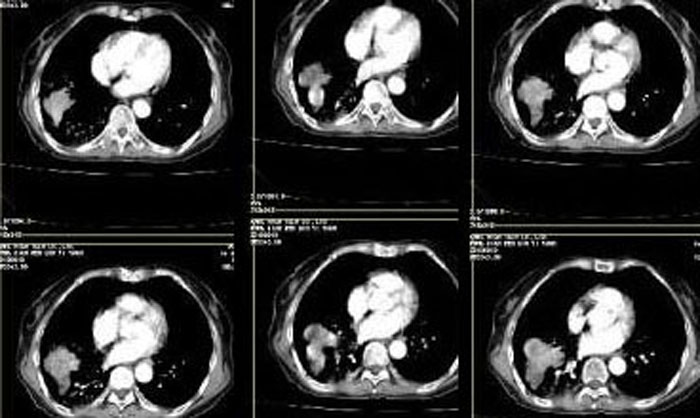

右肺下叶中央型肺癌伴下叶肺不张